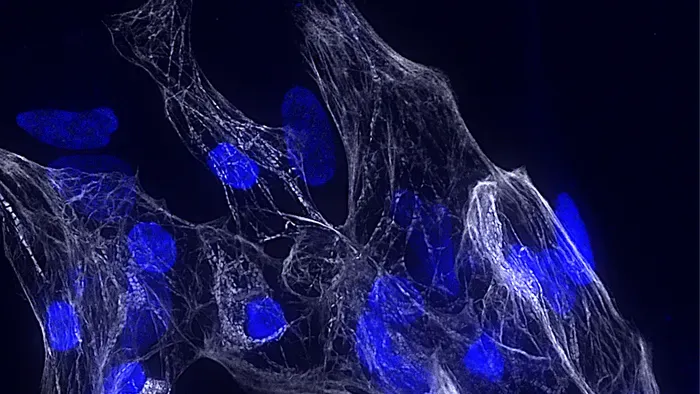

È stato individuato un gene finora sconosciuto nell'uomo che risulta essere di fondamentale importanza per la salute del cuore . Svolge infatti un ruolo chiave nello sviluppo delle cellule che lo fanno contrarre , i cosiddetti cardiomiociti . La scoperta, pubblicata sulla rivista Nature Communications, si deve al gruppo di ricerca italiano guidato dall'Università Sapienza di Roma, al quale hanno partecipato anche l'Istituto Italiano di Tecnologia e l'Istituto di Biologia e Patologia Molecolari del Consiglio Nazionale delle Ricerche, sempre di Roma.

"Questo gene appartiene alla categoria dei cosiddetti ' Rna non codificanti lunghi ', molecole che non danno origine a proteine ma regolano finemente l 'attività di altri geni ", afferma Monica Ballarino della Sapienza, che ha coordinato la ricerca. "Hscharme agisce come un vero e proprio architetto del genoma che guida la corretta attività dei geni del cuore : quando questo gene non funziona correttamente - prosegue Ballarino - le cellule non si sviluppano in maniera adeguata, con conseguenze sulla salute dell'intero organo".